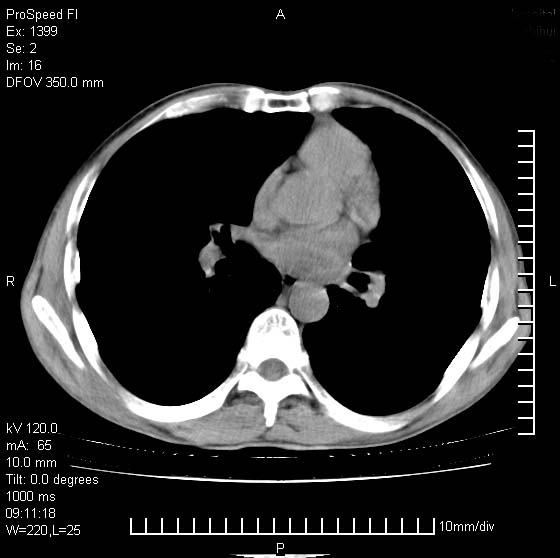

以下是引用卜一在2007-1-19 9:55:00的发言:[br]左肺沿胸膜下巨大肿块影,边缘呈分叶征,纵隔内见肿大淋巴结,右肺内另见一不规则结节影 .考虑:左肺周围性肺癌伴纵隔 右肺内转移.

以下是引用rgsyyf在2007-1-19 11:05:00的发言:[br]左肺上叶见形态不规则巨大软组织肿块影,边缘呈分叶征,纵隔内隆突下见肿大淋巴结,右肺内另见一不规则结节影 .考虑:左肺周围性肺癌伴纵隔即右肺内转移.